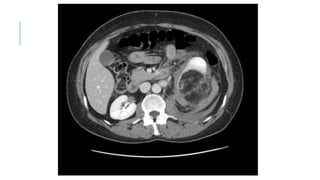

•Abdominal CT with contrast

CT can help detect Bowel injury in blunt trauma